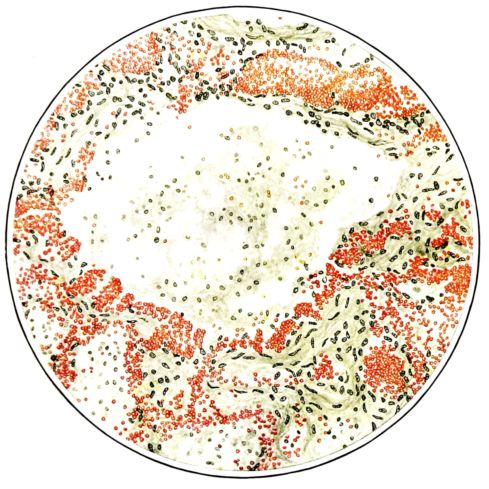

FIG. II. AUTOPSY NO. 98. DRAWING OF A SECTION THROUGH A TRACHEA SHOWING NECROTIZING HEMORRHAGIC INFLAMMATORY PROCESS OF THE MUCOSA.

The changes are less marked, perhaps, in the trachea than in its finer ramifications. The mucosa is constantly more or less destroyed and large areas, usually focal, are entirely devoid of their epithelial covering. This is replaced by a sparse exudate, composed largely of red blood cells, mucus, a small amount of fibrin, and nuclear fragments (Fig. II). It may dip into the submucosa for a short distance, but usually these indentures are associated with the ducts of the mucous glands into which the inflammatory reaction extends. A more striking feature than the exudate, however, is the edema and the congestion of the submucosa. The loose areolar tissue of the submucosa is spread widely apart, and throughout it distended blood vessels are very conspicuous. Occasionally such a vessel is broken and actual hemorrhage appears in the submucosa. Occasionally, too, the inflammation extends down the duct to the mucous gland itself, and here, also, aplastic inflammatory reaction is evident, inasmuch as the acini now stain intensely red with the cells undifferentiated from each other and specked here and there by broken remains of the dead nuclei (Fig. III). After the disease has continued for a short period, even at the end of five or six days, some regeneration of the epithelial lining may be seen (3) (Fig. IV). But despite this, the acute picture persists, and there goes on, side by side, an attempted repair characterized by epithelial regeneration and the same evidence of acute change. Since the lesion is essentially a superficial one, scars or contractures of any extent are not encountered in the trachea, even in examples of the disease that have ended fatally only after many weeks.[4]